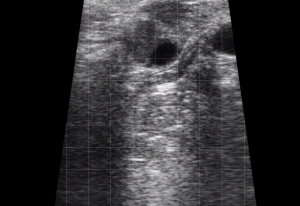

SIMON Ultrasound Database

This ultrasound database is a free resource for students and doctors!

Our collection includes videos of dogs, cats, horses, cows, humans, and many other species!